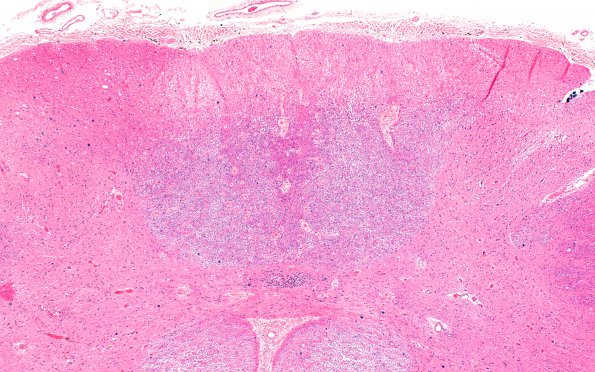

Washington University Experience | MYELIN (IMMUNE-MEDIATED) | MS - Spinal Cord | 1C1 Multiple Sclerosis, 50 yr Hx (Case 1) N17 Spinal cord H&E 4X

1C1-3 The dorsal column of one section shown in the previous whole mount series is shown at higher magnification (4X) stained for H&E (1C1), LFB-PAS (1C2) and Bielschowsky (1C3). ---- The dorsal columns are quite pale with significant atrophy and increased numbers of corpora amylacea. Notice the absence of inflammatory infiltrate (H&E).